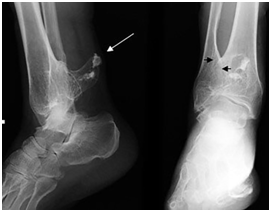

A 69year-old man with a known HME, admitted to orthopedia clinic for right ankle pain that was serious especially at standing position. At physical examination, he had restricted joint movements during abduction and adduction. There was a hard, fixed swelling localized superiorly to the shin, measuring 3x4x4cm. Patient was subjected to anteroposterior and lateral radiography of ankle joint. Radiography showed a well defined bony lesion superposed to the posterior aspect of distal tibiofibular metaphysis with a thin sclerotic rim and posterior edge calcification (Figure 1). There was also tibitalar tilt (valgus deformity) at AP graphy.

Figure 1 AP and lateral radiographs of ankle showing a well defined osteochondroma with a calcified cap, arising from posterior aspect of both tibia and fibula (white arrow). Cortices of tibia and fibula are indistinct at the tumor level, suggesting a synostosis (black arrows). Tibiotalar tilt is also well depicted on AP graphy.